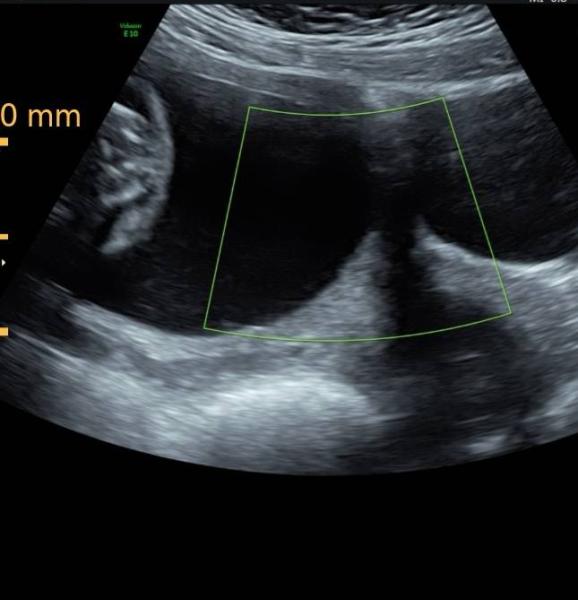

Ich dachte ich lad hier mal ein paar Bilder hoch. Durfte beim Ultraschall mitfilmen und hab Screenshots gemacht.

Ich dachte ich lad hier mal ein paar Bilder hoch. Durfte beim Ultraschall mitfilmen und hab Screenshots gemacht.

Beim Bild oben rechts würde ich deutlich Mädchen sagen, sah bei meiner Tochter sehr ähnlich aus aber die anderen Bilder verunsichern mich, ob da vlt. doch noch was ist ![]()

![]() seht ihr da immer noch ein Mädchen?

seht ihr da immer noch ein Mädchen?

Im ultraschall hat mann meiner meinung nach ganz deutlich gesehen das das junge ist und meine ärztin sah auch ganz sicher aus doch hat trozdem erstmal nur 70% tandez auf junge gegeben und in 2 wochen will sie noch mal schauen das ist mein 3. Kind und ich weiß das meine beiden mädels ganz anders aussahen ![]() könnt ihr mir bitte sagen bin ich verrückt oder sieht ihr auch junge auf dem ultraschallbild .danke

könnt ihr mir bitte sagen bin ich verrückt oder sieht ihr auch junge auf dem ultraschallbild .danke

Hallo zusammen Kann mir jemand sagen was auf diesem Ultraschallbild zu erkennen ist??

Hallo Zusammen Was meint ihr zu meinem Ultraschallbild? :)